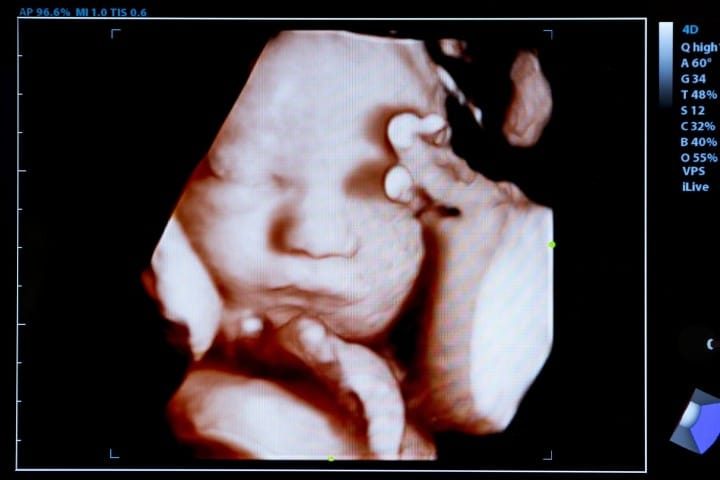

According to a summary of the documents, the aims of the project listed in the original 2015 proposal filed by Pitt were to “develop a pipeline to the acquisition, quality control and distribution of human genitourinary [urinary and genital organs and functions] samples obtained throughout development (6-42 weeks gestation) … [and] generate an ongoing resource to distribute fresh developmental human genitourinary samples from various stages (6-42 weeks) to the GUDMAP [GenitoUrinary Development Molecular Anatomy Project] Atlas projects.” 42 weeks of gestation means the very final stage of fetal development. Most pregnancies last 37 to 42 weeks. Fetal viability, or the point at which a baby can be resuscitated at delivery and can survive without significant morbidity, is generally considered 24 weeks gestation. The Christian Post observes that in 1973, when Roe v. Wade was decided, 28 weeks was seen as the point of viability. By 1992, the term “viable” applied to babies born at 23 or 24 weeks gestation. Today, it is argued fetus may survive, with medical help, at 15 weeks of gestation.

Further, it was revealed the university advertised its capabilities in providing human tissue by stating it “takes steps” to “ensure the highest quality biological specimens.” It is specified, for example, that “warm ischemic time” (per NIH, the time a tissue, organ, or body part remains at body temperature after its blood supply has been reduced or cut off but before it is cooled or reconnected to a blood supply) is “kept at a minimum.” In the documents, Pitt explains the procedure used to obtain the tissue is a labor induction, meaning a stimulation of uterine contractions during pregnancy before labor begins on its own to achieve a vaginal birth. In a press release, the CMP noted that “if the fetus’ heartbeat and blood circulation continue in a labor induction abortion for harvesting organs, it means the fetus is being delivered while still alive and the cause of death is the removal of the organs.”